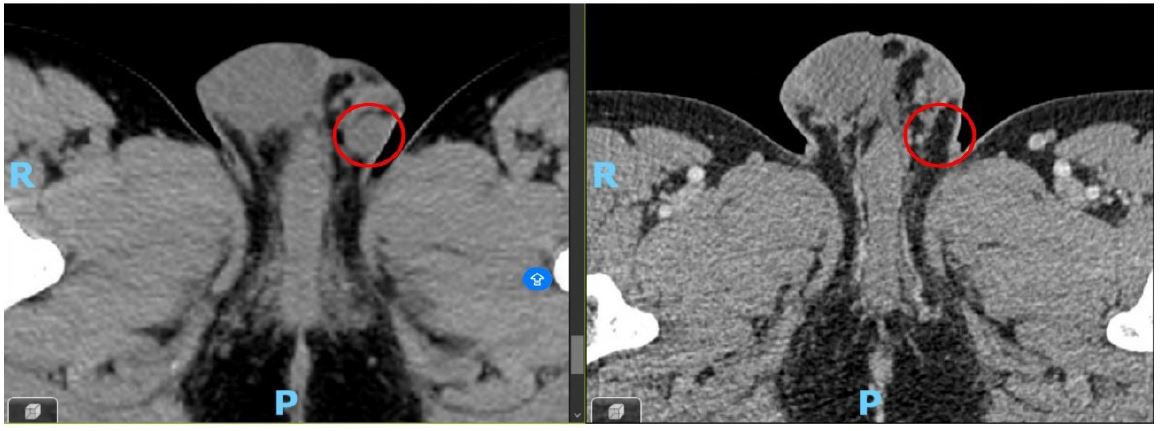

Given persistent respiratory symptoms without evidence of infection, a chest Computed Tomography (CT) scan was conducted, revealing a solid lesion in the right lower lobe suggestive of a primary tumor, accompanied by bilateral hilar lymphadenopathies. Subsequent Positron Emission Tomography-Computed Tomography (PET)-CT demonstrated elevated metabolic activity in the pulmonary lesion, bilateral hilar, cervical, mediastinal, and left inguinal lymphadenopathies, and a probable metastatic left scrotal lymph node (Figure 2).

Figure 2: The left image presents a CT scan revealing a right testicular nodule, while the right image shows the corresponding PET scan, which exhibits increased metabolic uptake at this site, consistent with malignancy.